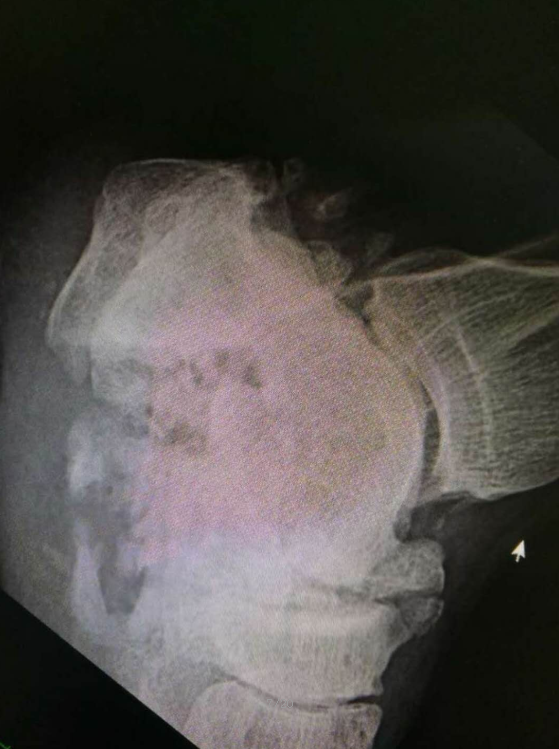

病例一患者男性29岁,左侧跟骨骨折术前X片示,左足跟骨骨折

轴位像可见跟骨骨折轻度内翻移位

CT显示跟骨骨折移位 跟骨术后侧位

骨折复位固定好,高度恢复,盖氏角和鲍曼氏角恢复。

轴位像,跟骨内翻纠正,跟骨宽度恢复满意